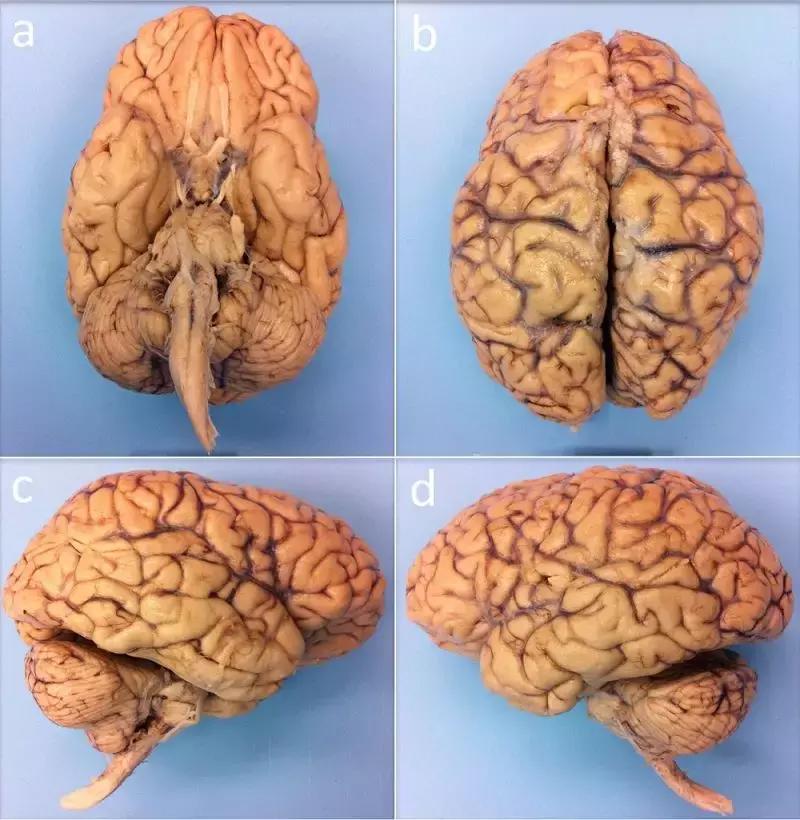

为了获得一份完整且详细的大脑三维图像,波士顿麻省总医院及其它地方的研究人员,将目标锁定在一名死于病毒性肺炎的 58 岁女性大脑标本,其大脑重达 1210克(正常范围 1200 至 1500 克),死后 14 小时一直固定在 10% 的福尔马林中。

图 | 体外核磁共振成像的人脑标本,下方(a)、上方(b)、右侧(c)和左侧(d)角度(来源:B.L. EDLOW ET AL/BIORXIV.ORG 2019)

而且这个来自捐献的大脑样本被认为是健康的,因为该女性没有神经系统疾病病史,死于非神经病因。

在扫描开始之前,大脑标本已经在固定剂中保持了 35 个月,之后研究人员将大脑标本放入一个定制的球形聚氨酯盒子,以让大脑保持静止并让干扰的气泡逸出。

然后,牢固包裹的大脑进入一台7T超强核磁共振扫描仪中,进行了长达近 5 天的扫描成像,获得了体外完整人脑标本前所未有的 100 微米分辨率空间图像。